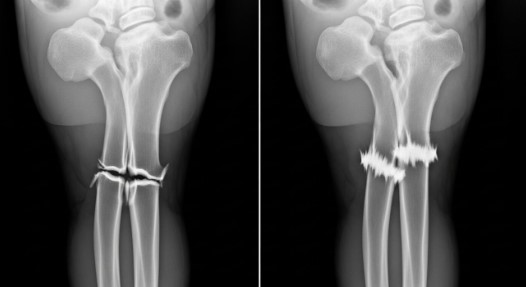

O produto foi testado em mais de 150 pacientes em hospitais da China e obteve resultados positivos em todos os casos. Um deles envolveu um trabalhador com uma fratura grave no antebraço, que normalmente demandaria uma operação extensa.

Com a cola, os fragmentos ósseos foram fixados em minutos, e após três meses o paciente já havia recuperado totalmente os movimentos do punho.